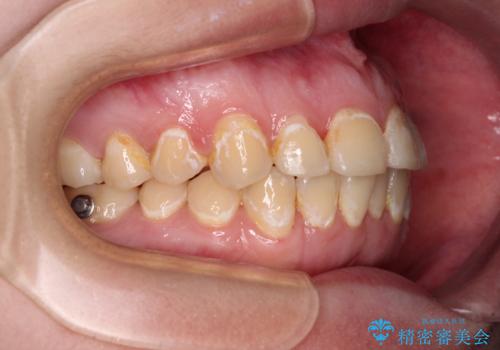

- 前歯のデコボコとクロスバイトが気になり、インビザラインによる矯正治療を希望して来院された患者様です。

上顎側切歯(上の真ん中から2番目の歯)が舌側転位している場合、無理して動かそうとすると歯髄壊死を起こすリスクが高い印象があります。

インビザライン単体でも治療は可能ですが、安全策としてインビザラインで歯列を移動する前に上顎前歯をワイヤー矯正で整え、その後上下歯列をインビザラインにて矯正治療を行うこととしました。

舌側転位している側切歯特有の、切縁の位置が不揃いであったり、根元が内側に引っ込んだ状態であったりという、インビザライン独特の仕上がりになることなく、きれいに整った歯列とすることができました。